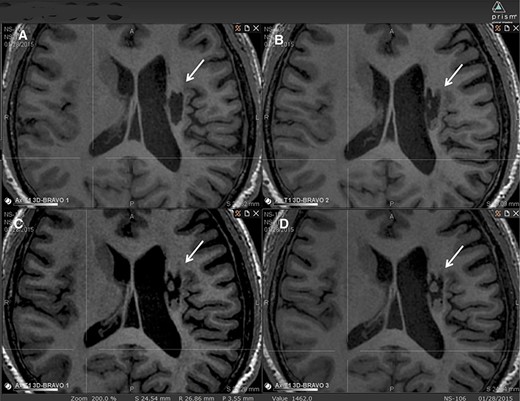

圖中顯示了B組 (#106) 受試者在T1MRI上隨時(shí)間的變化。

(A):基線時(shí),(B) 6個(gè)月隨訪時(shí),(C) 12個(gè)月隨訪時(shí),(D) 24個(gè)月隨訪時(shí)。箭頭表示梗塞腔。

可以看到兩個(gè)組織團(tuán)塊,在基線時(shí)不存在,推測(cè)是來自植入的NSI-566,隨著時(shí)間的推移,它們似乎慢慢填滿了腔體。